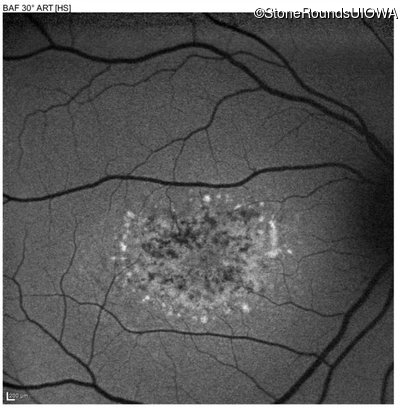

This 16 year old female first had difficulty seeing the blackboard at age 9. Her eye doctor at the time felt at the time that she was "faking it". More recently her eye doctor told her she would be blind by age 20 and suggested she get a seeing eye dog.

| AR Stargardt Disease | ABCA4 | Asp507Tyr GAT>TAT | IVS40+5 G>A | AR |